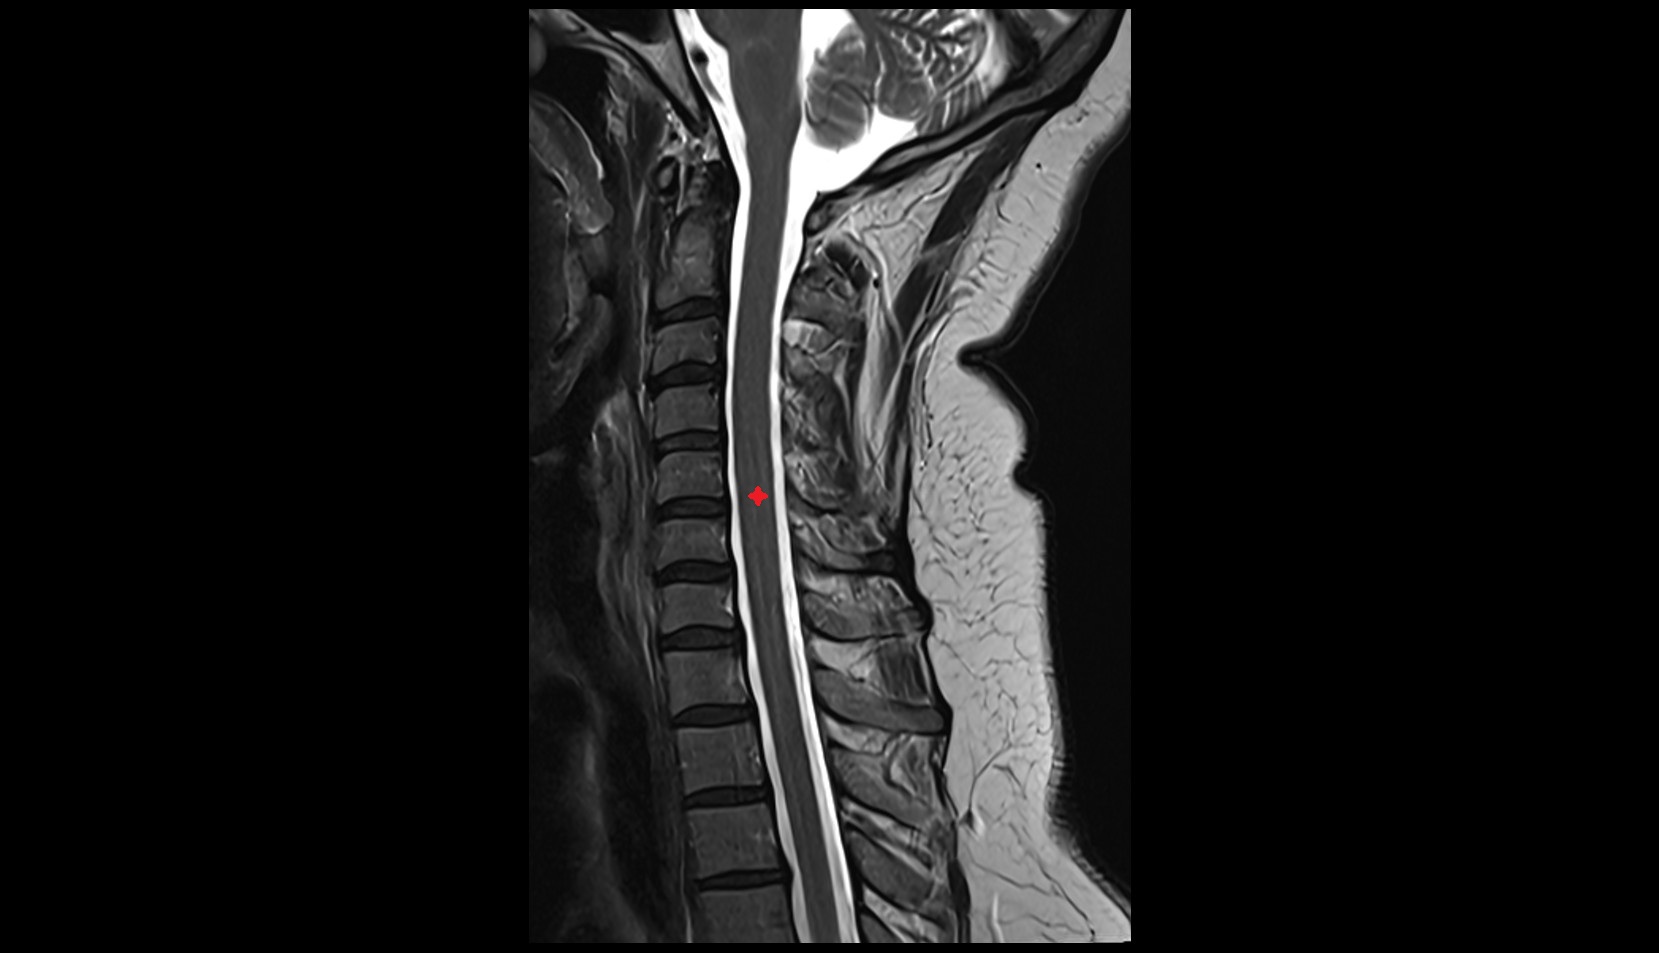

- Spinal cord

- Upper cervical spinal cord

- subarachnoid space of spinal cord